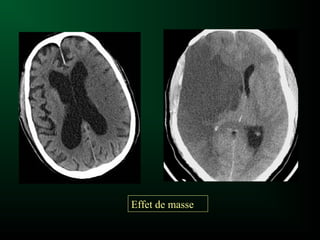

Effet de masse

Processus expansif

– Tumeur, abcès, hématome, kyste, etc...

Conséquences:

– Déplacement: ligne médiane, ventricules, parenchyme

– Compression des espaces sous arachnoïdiens

Risque = engagement

Effet de masse :

engagement sous falcoriel

Engagement sous-falcoriel

Effet de masse Processusexpansif – Tumeur, abcès, hématome, kyste, etc... Conséquences: – Déplacement: ligne médiane, ventricules, parenchyme – Compression des espaces sous arachnoïdiens Risque = engagement